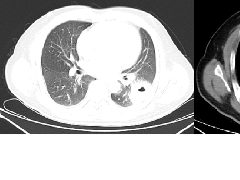

张力性纵隔气肿影像表现及严重度分级  迅速增大的肺部结节,首先考虑良性,确诊需要肺穿

迅速增大的肺部结节,首先考虑良性,确诊需要肺穿  肺隔离症:易误诊为肺癌的占位性病变,肺穿刺禁忌!

肺隔离症:易误诊为肺癌的占位性病变,肺穿刺禁忌!  肺段与肺内管道应用解剖